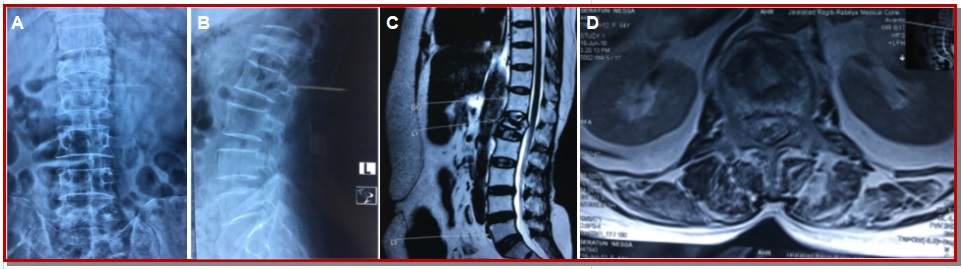

The aim of this study is to evaluate balloon kyphoplasty as a surgical option for osteoporotic thoracolumbar compression fracture. The study was conducted on 30 patients from January 2014 to December 2017. The anterior vertebral height, kyphotic angle and functional evaluation by Oswestry disability index (ODI) and visual analogue scale (VAS) score were recorded preoperatively, immediate post-operatively at 3, 6, 12 months and yearly then on. All patients showed improvement in mean kyphotic angle from 16.4 ± 3.5 to 5.6 ± 1.7 post-operatively and 8.4 ± 1.6 at final follow-up. There was significant increase in mean anterior vertebral height from 51 ± 7.3% before surgery to 75.5 ± 7.4% at one day after surgery and 71.2 ± 3.2% at the last follow-up. There was significant improvement in mean VAS score from 8.1 ± 0.9 before surgery to 2.2 ± 0.4 at one day, and 2.4 ± 0.3 at final follow-up. The improvement in patients’ ODI score after surgery from 71.4 ± 3.4 to 26.0 ± 4.8 at one day and 21.2 ± 5.5 at final follow-up was noted. The mean operating time was 45.5 ± 15.5 min for each vertebra. Within first day of surgery improvement in pain relief and mobility was experienced by all patients. The orthopedic balloon ruptured in one patient and it was replaced then procedure was continued with no complications. There were no neurological complications in all cases and there was no infections and any occurrence of symptomatic pulmonary embolism. In conclusion, balloon kyphoplasty is a good minimally invasive procedure where along with reduction of pain and disability there is also restoration of sagittal alignment post-operatively.